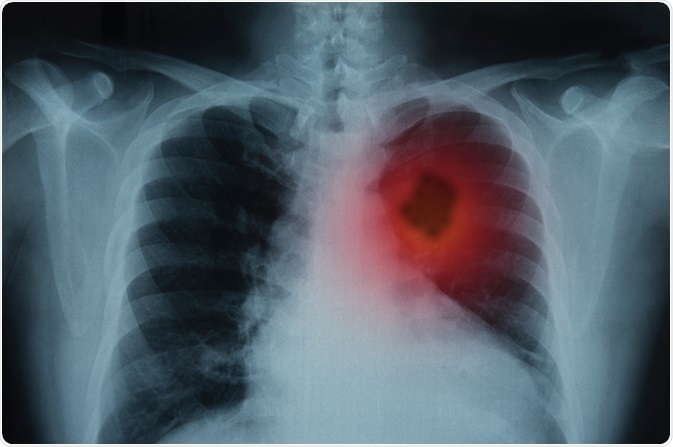

Lung Cancer

Image Credit: Create Jobs 51/Shutterstock.com